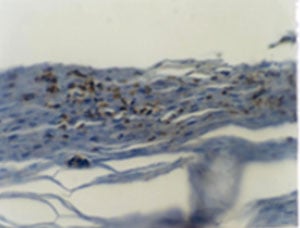

(The antibody was used to detect IL-8 expression in the stratum corneum of psoriatic skin tissue. The image below shows the result of detecting with anti-IL-8 clone 60, biotinylated 2rd antibody and avidin-HRP. The specimen was stained with DAB substrate for 5~10 min, and counter-stained with hematoxylin.)